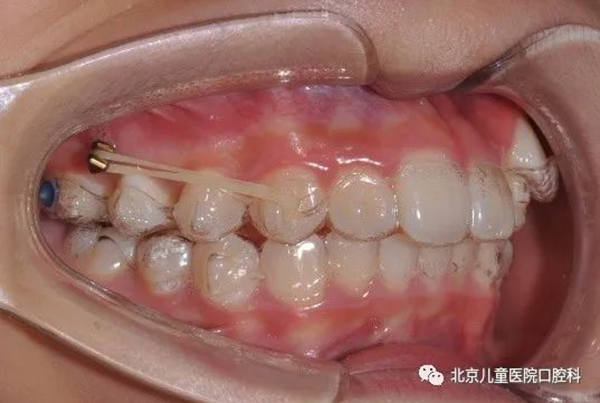

骨钉是正畸过程中固定于骨组织上的小直径、头部独特设计的微螺钉,又叫支抗钉、种植钉。通常暂时性植入牙槽骨,矫正结束时取出。

骨钉的直径从1.2mm~2.7mm不等,矫正牙齿常用1.3mm~1.6mm直径的骨钉,长度多为4mm~12mm,目前正畸常用6mm~10mm长度的规格。由此可见我的身材很迷你。

骨钉顶部的形状设计各种各样,如托槽式、牵引钩式、纽扣式等等,满足正畸临床多样化的需求。

打骨钉有什么作用呢?简单说,骨钉是正畸移动牙齿过程中引入的外援,锚定于牙槽骨中,适用于直接移动牙齿,或承担移动牙齿产生的反作用力,在专业术语中称为“支抗”。在以往没有我的情况下,反作用力会直接或间接作用于不希望发生移动的牙齿上,对正畸疗效产生不良影响。我可以为大多数正畸患者提供足够的支抗, 获得医患均满意的疗效,且植入和取出操作简单, 植入部位灵活,因此临床应用日益广泛。